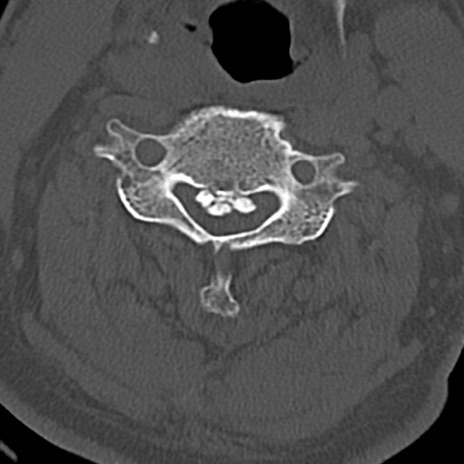

頚椎CT

横断像